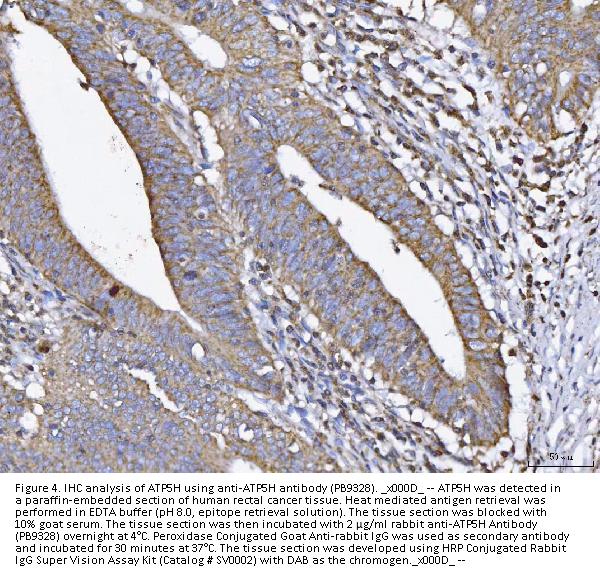

Immunohistochemistry (Paraffin-embedded Section), 2-5μg/ml